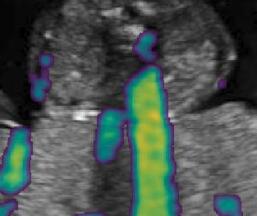

Fig. 6 compares the shadow confidence maps of the state-of-the-art methods and the proposed methods. RW and have the same parameters as used for Table I. The shadow confidence maps of the baseline, the proposed method and the proposedAG method are generated directly from input shadow images by confidence estimation networks. Overall, the proposed method and the proposedAG method achieve more visually reasonable shadow confidence estimation than the baseline and the state-of-the-art on different anatomical structures shown in Fig. 6. The proposed method and the proposedAG method are able to highlight multiple shadow regions while the RW algorithm shows limitations for most cases, especially for disjoint shadow regions.

Row I in Fig. 6 shows a fetal brain image from . The confidence estimation of shadow regions from the baseline, the proposed method and the proposedAG method are similarly accurate since we use fetal brain images to train the confidence estimation networks in these three methods. These outperform [16] and [22]. Rows (II-IV) in Fig. 6 show shadow confidence maps of non-brain anatomy from , including lips, abdominal and cardiac. The baseline failed on unseen data during inference. However, the proposed methods are able to generate accurate shadow confidence maps because of the generalized shadow features obtained by the shadow-seg module. Furthermore, the “Lips” example shows that our method is capable of detecting weaker shadow regions that have not been annotated in manual segmentation. This indicates that the confidence estimation network has learned general properties of shadow regions.